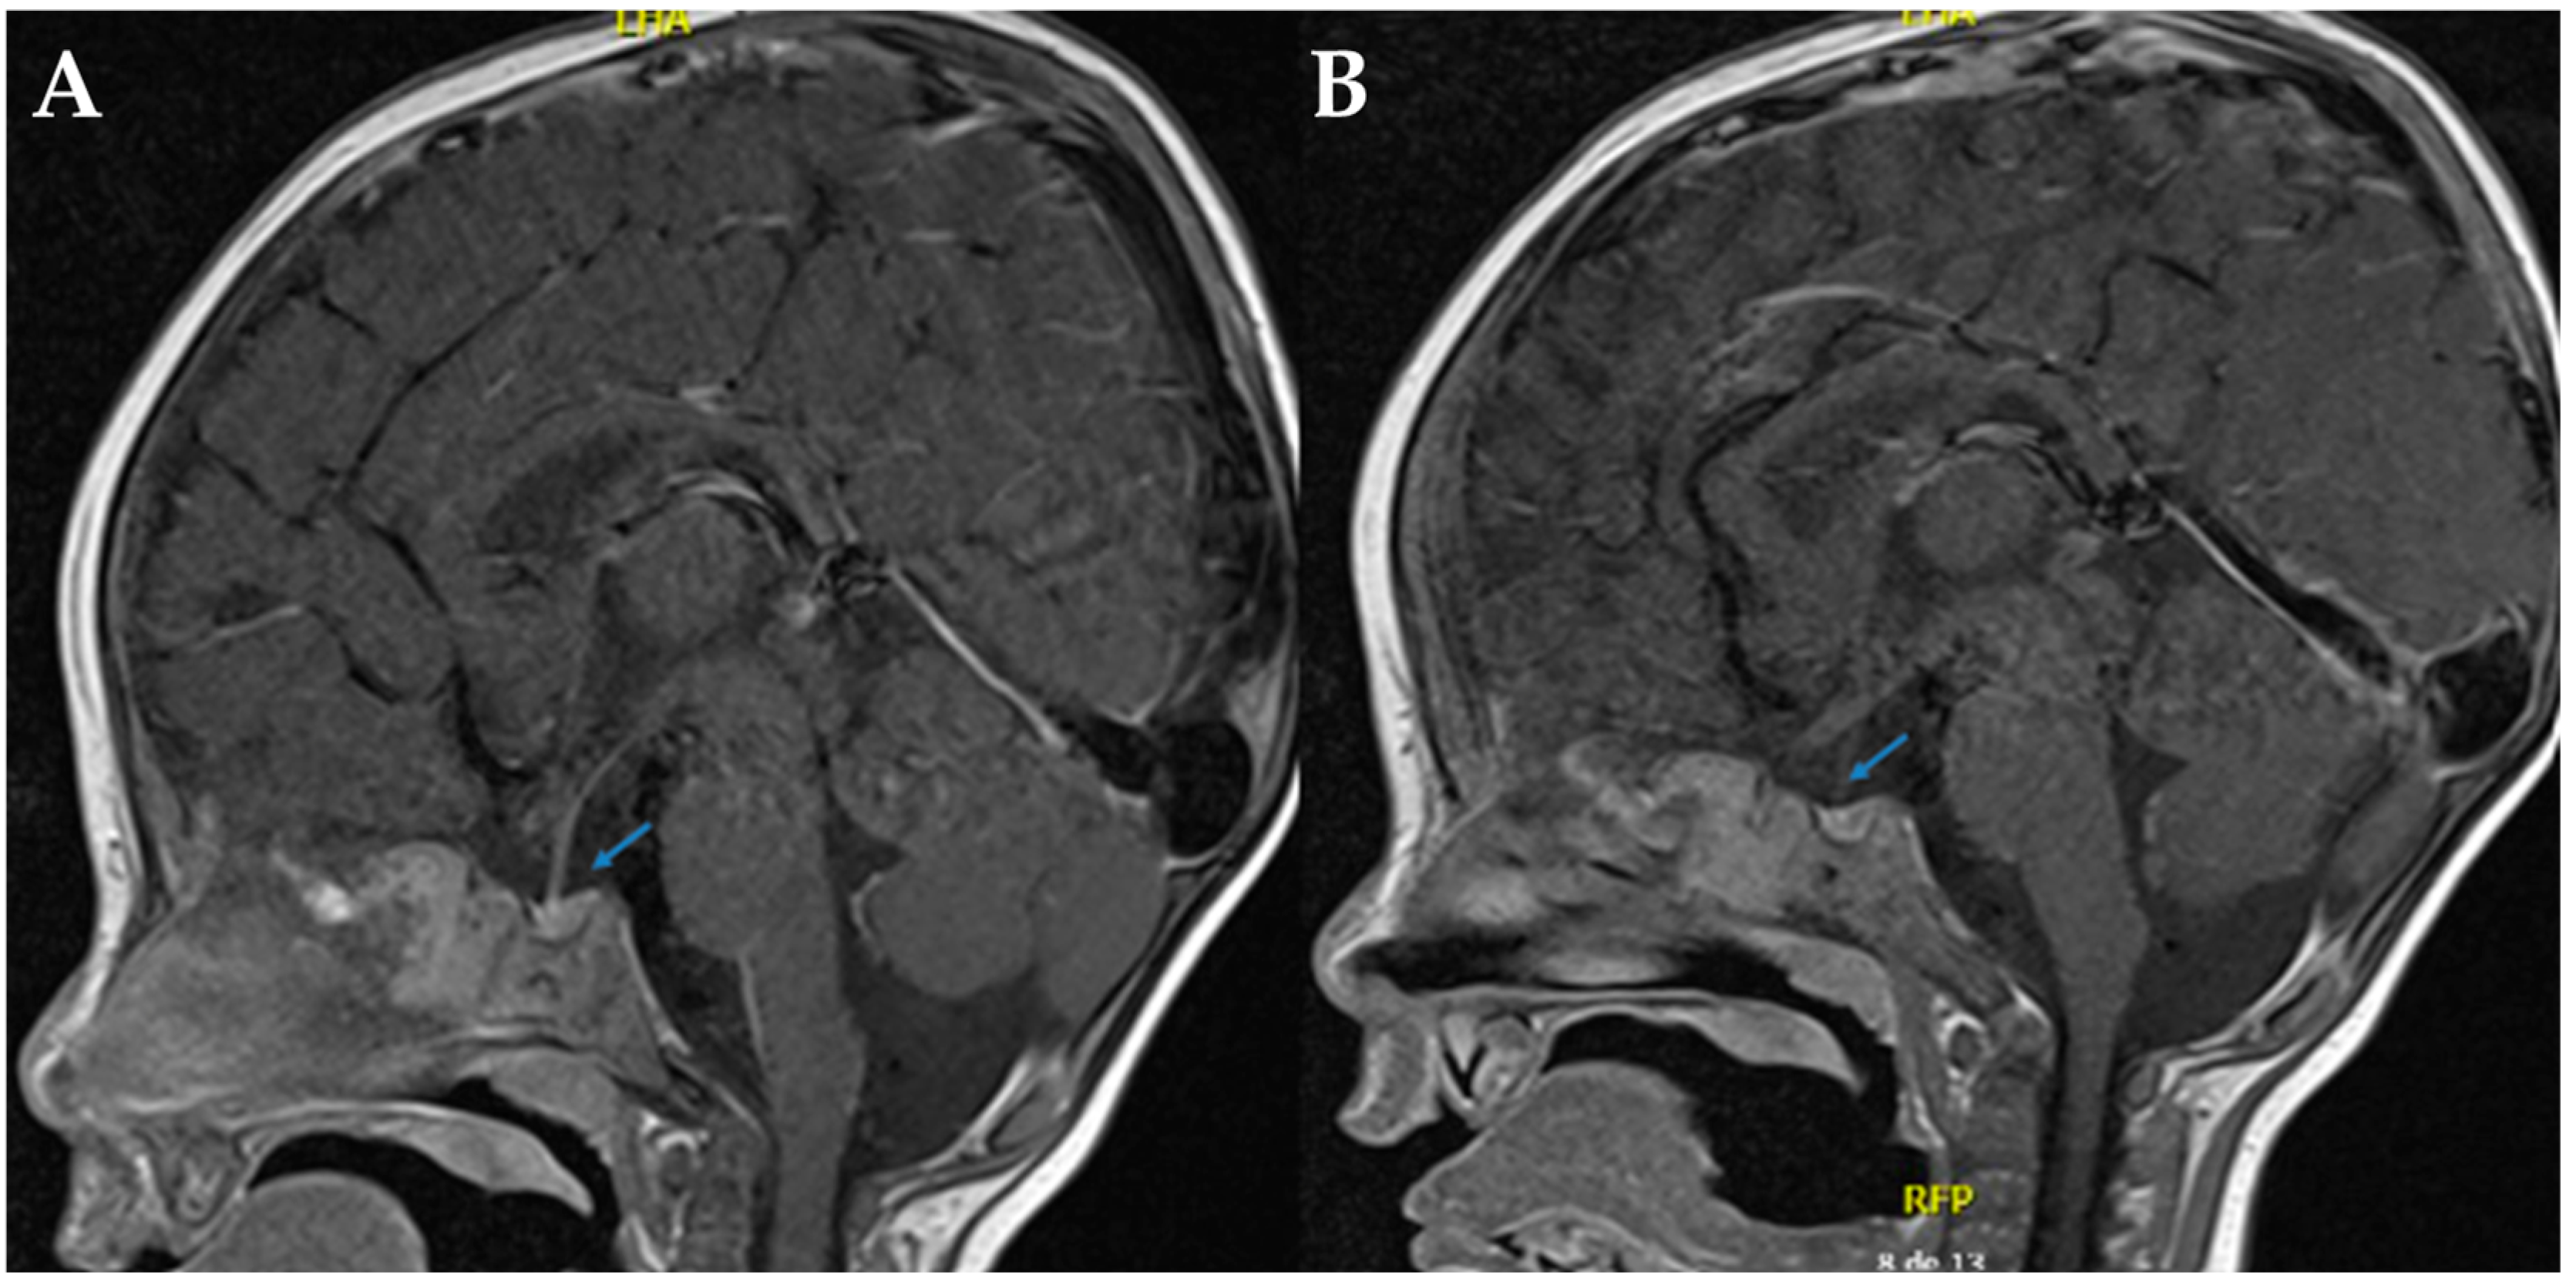

Magnetic resonance imaging (MRI) of the sella turcica revealed the absence of the posterior pituitary bright spot, reinforcing the suspicion of mixed diabetes insipidus (See Figure 1). Despite continued desmopressin administration, the patient exhibited no improvement in polyuria or hypernatremia. After a comprehensive evaluation by pediatric nephrology and endocrinology, it was concluded that the radiological findings did not confirm concomitant CDI. Consequently, desmopressin therapy was discontinued.

Initially, CDI was suspected due to the absence of a visible neurohypophysis on neuroimaging. However, the lack of clinical or biochemical response to desmopressin administration, combined with the confirmatory genetic test, ultimately established the diagnosis of NDI. This has been reported previously in other cases with NDI [20,21] and is possibly related to chronic dehydration with subsequent depletion of pituitary AVP, proposing that the bright signal in neurohypophysis reflects neurosecretory granules containing vasopressin, and this signal depends on the production and secretion of AVP [21]. Nevertheless, idiopathic absence of this hyperintensity has also been proposed [21] and can even be physiologically absent in ~10% of healthy individuals [21]. Therefore, MRI does not necessarily reflect the origin of DI (either CDI or NDI) and should only be performed in diagnosed cases of CDI [21]. This highlights the critical value of molecular testing in cases with inconclusive clinical findings or overlapping phenotypes.

Figure 1. Sella turcica in T1 sagittal brain MRI. (A,B). In both sections, the arrows indicate the absence of the hyperintense signal characteristic of the neurohypophysis, which is compatible with its radiological absence.